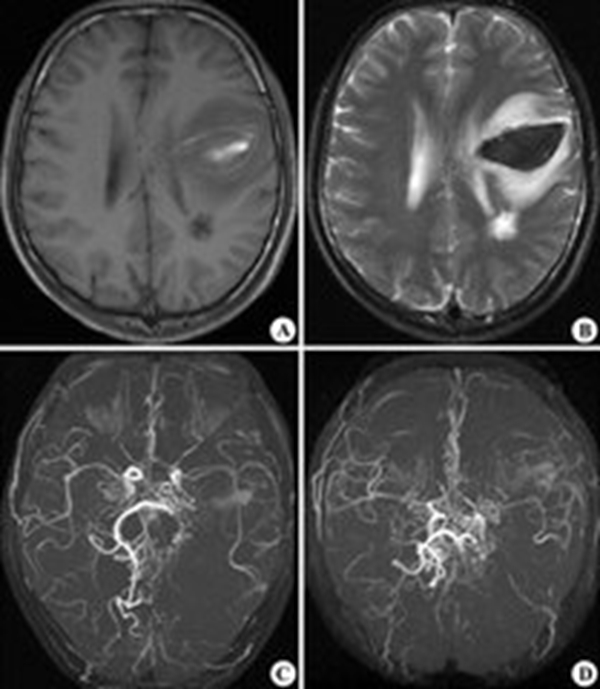

煙霧病圖片

早期煙霧病

左側煙霧病

煙霧病造影表現

煙霧病造影圖

煙霧病造影

煙霧病血管造影